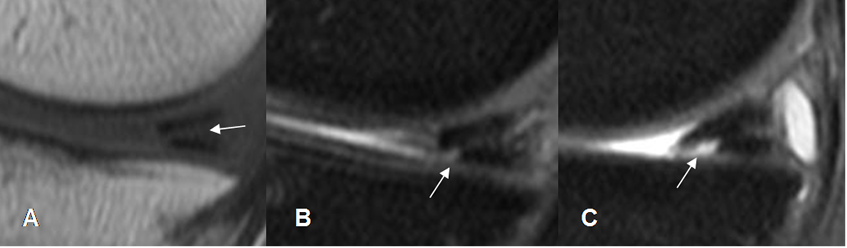

Fig 68. Ruptura meniscal dudosa.

A y B: RM sagital en T1. Imágenes hiperintensas y en sentido oblicuo, sobre el cuerno posterior del menisco interno. La completa comunicación con el borde inferior, es difícil de determinar con certeza.